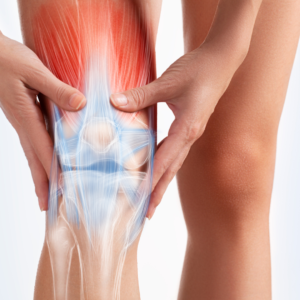

Are stiff joints or discomfort limiting your mobility? Whether it’s your knees, shoulders, or hips, joint issues can make it harder to stay active and enjoy life.

At Prolean Wellness, we offer regenerative wellness solutions designed to support your body’s natural recovery processes. These innovative, non-invasive therapies may help promote joint flexibility, encourage movement, and assist in long-term wellness—without surgery or extended downtime.

Our advanced wellness therapies use biologically active components to support natural tissue function and recovery. These treatments are designed to complement your body’s own healing mechanisms, providing a proactive approach to maintaining joint health and mobility.